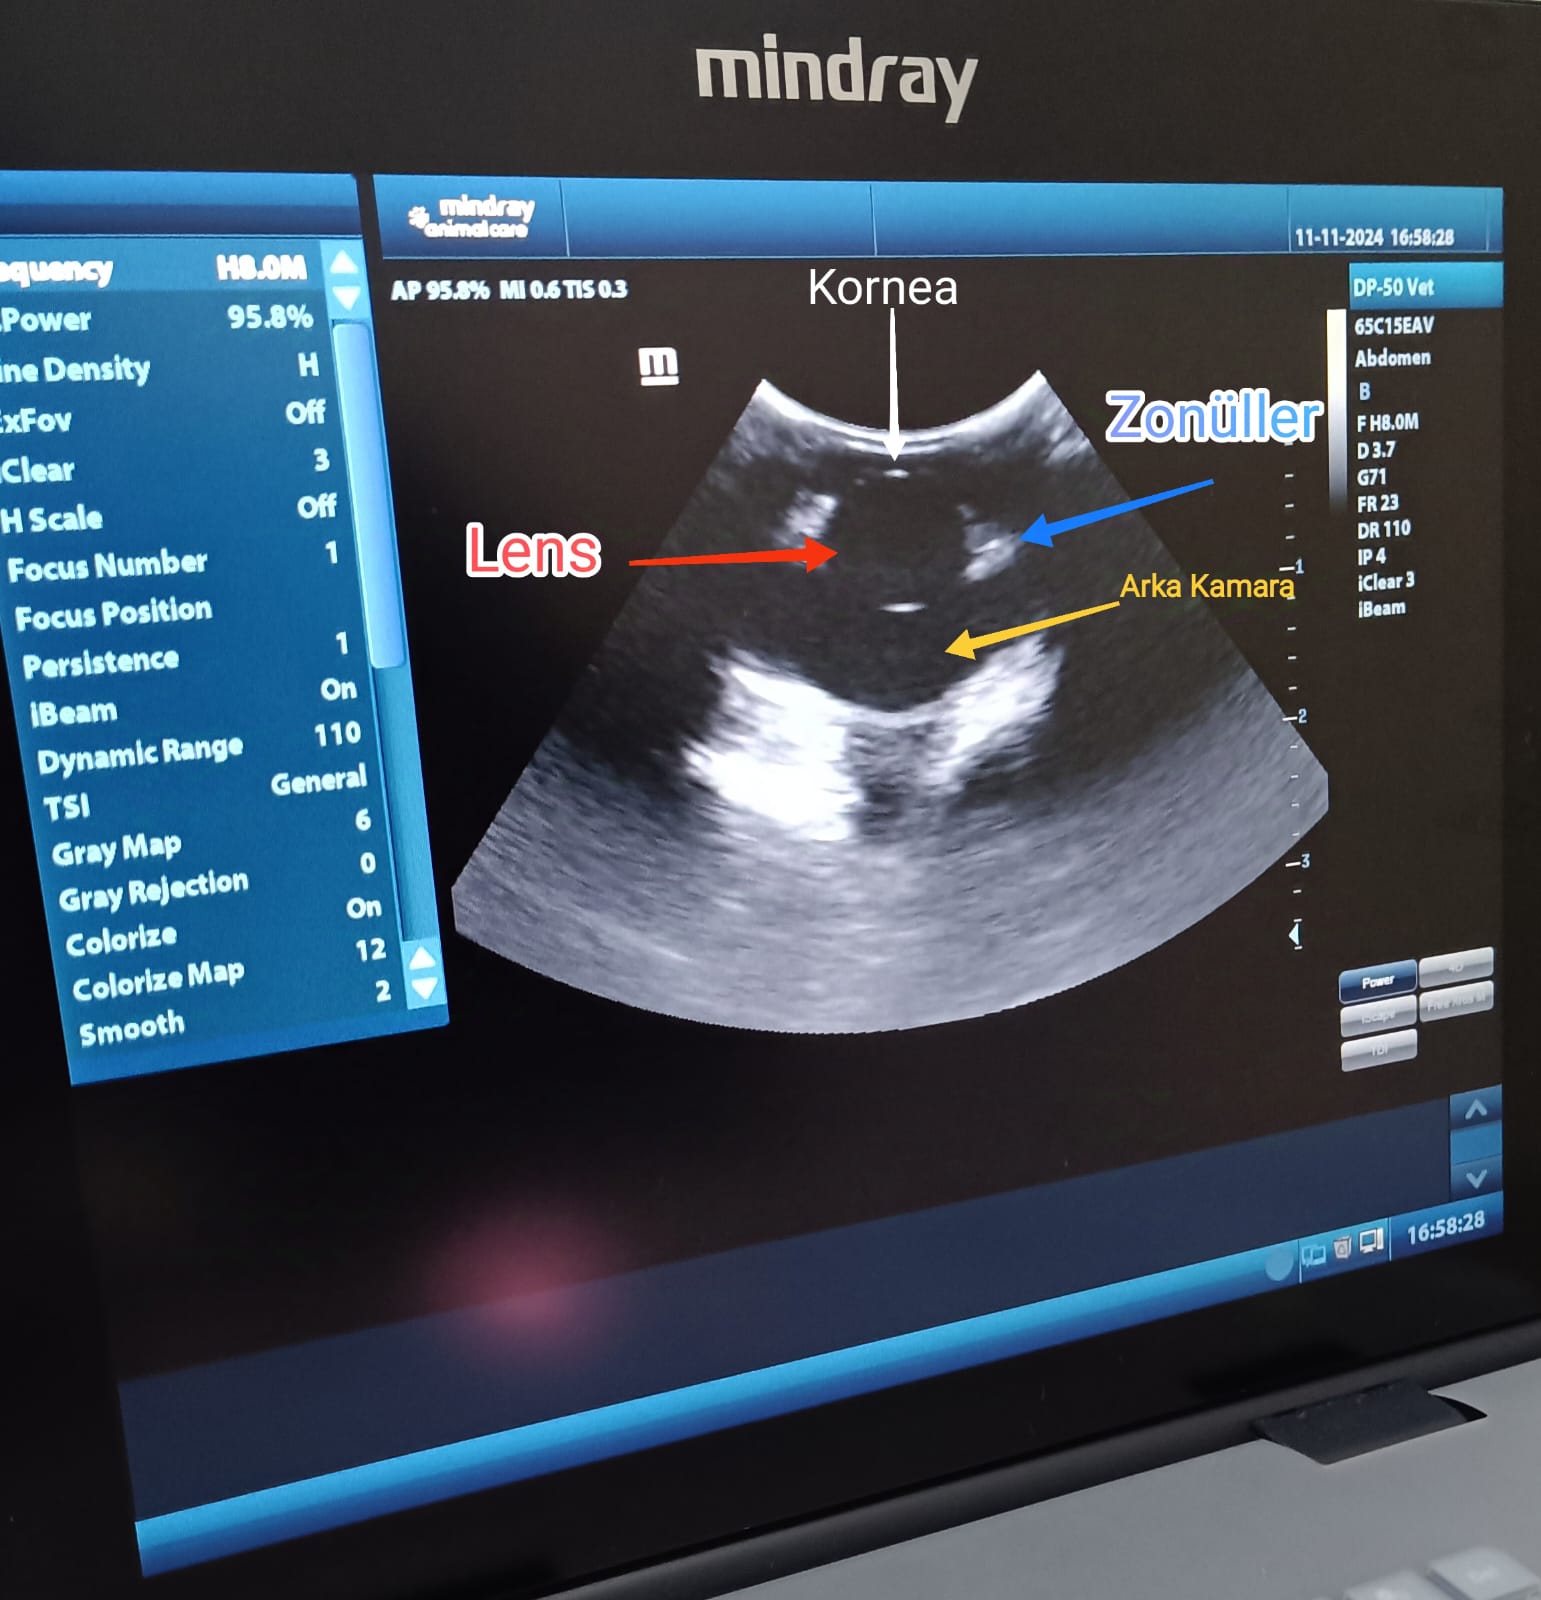

Radyoloji Hizmetleri

Tecrübeli kadromuzla ve gelişmiş röntgen/ultrason hizmetleriyle hızlı ve doğru teşhis imkanı sunuyoruz.